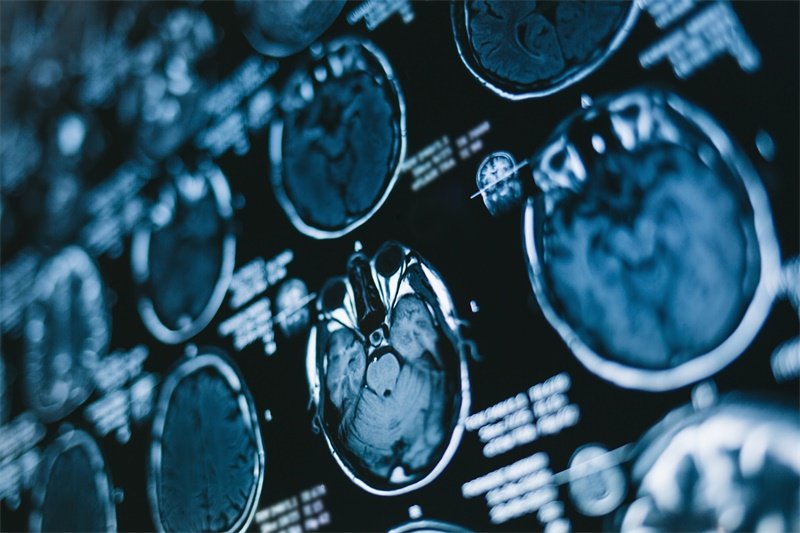

鞍区占位与面神经的关系?在神经外科领域,鞍区占位是一种较为常见的病症,指的是脑部鞍区内的肿块或病变,这个区域涉及到重要的神经结构,包括脑下垂体和视神经。作为患者及其家属,了解鞍区占位对面神经的潜在影响,是非常重要的。面神经的损伤或受压,会导致面部的运动功能减弱,甚至引发更为严重的问题。而这一切,都与鞍区所占据的空间以及它对周围神经结构的影响息息相关。

鞍区占位对面神经的影响

鞍区占位对面神经的影响是一个值得关注的问题。因为面神经的功能与表达和运动有密切联系,以下是几点主要影响:

压迫导致的面神经损伤

当鞍区出现占位,肿瘤或病变可能会压迫面神经。这种压迫会导致面神经的功能紊乱,表现为面部肌肉的无力或麻痹,影响日常的面部表情和活动。

并非所有的鞍区占位都会影响面神经。只有当占位显著增大,压迫到面神经时,才有可能引发相关症状。因此,建议定期进行头部影像学检查,及时发现问题并处理。